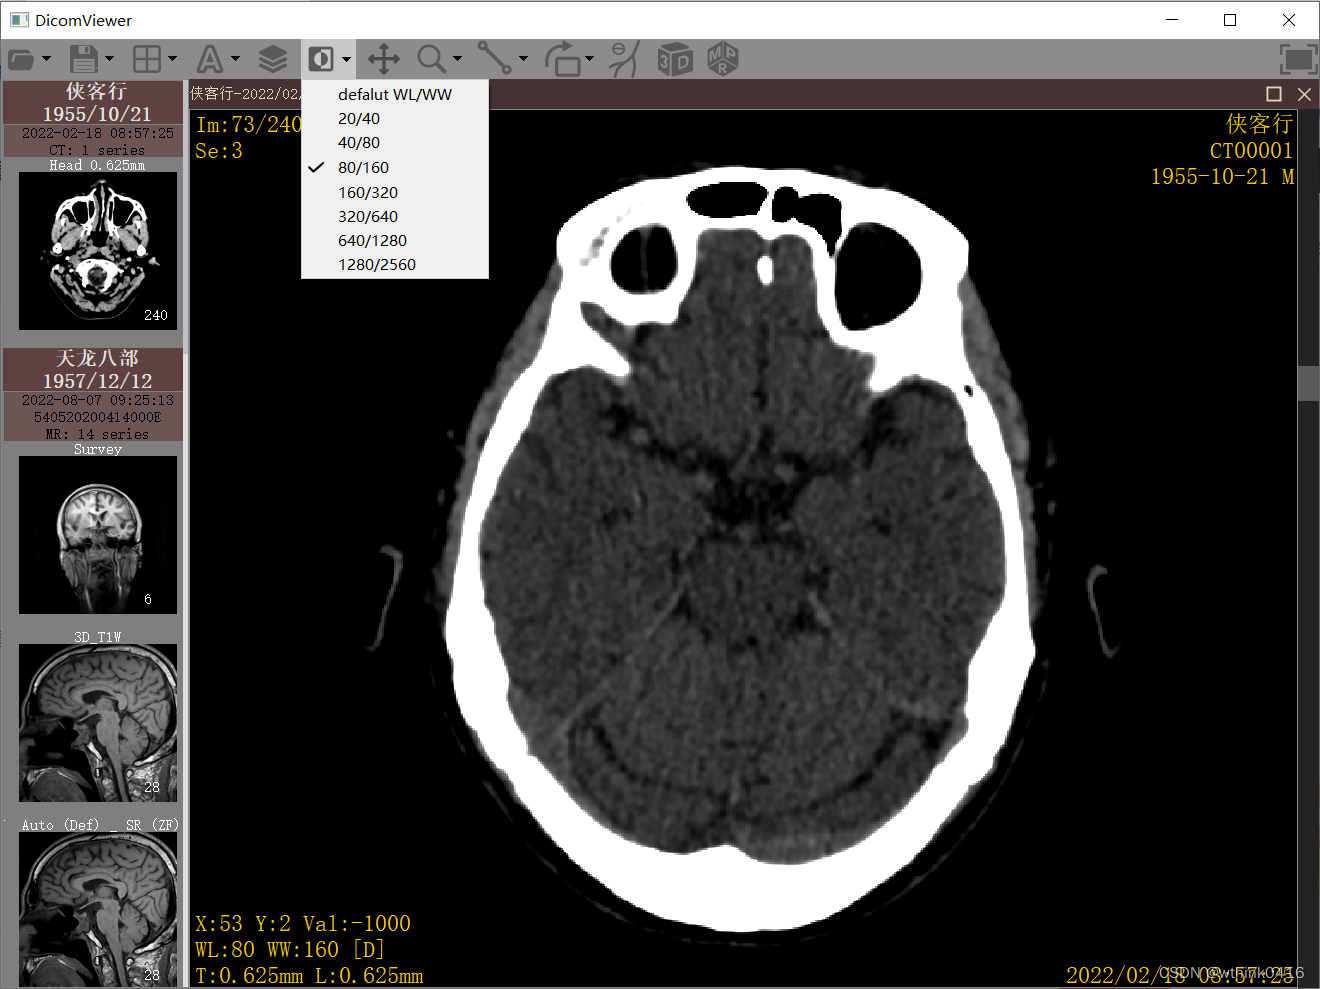

5、点击![]() 调整窗宽窗位图标后,鼠标左键按下同时移动,左右移动调整窗宽,上下移动调整窗位,下拉菜单可预设一些窗宽窗位

调整窗宽窗位图标后,鼠标左键按下同时移动,左右移动调整窗宽,上下移动调整窗位,下拉菜单可预设一些窗宽窗位